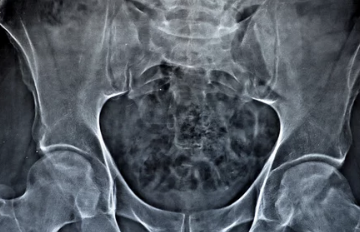

고관절은 우리 몸에서 가장 큰 관절이며, 걷기, 달리기, 서기 등 다양한 활동에 중요한 역할을 합니다. 하지만 나이가 들면서, 또는 특정 질환으로 인해 고관절에 통증이 발생할 수 있습니다. 오늘은 고관절 통증 증상 원인 TOP5 총정리 해드리겠습니다.

고관절은 다리와 골반을 연결하는 중요한 관절이며, 걷기, 뛰기, 앉기 등 다양한 활동에 중요한 역할을 합니다. 고관절 통증은 다양한 원인으로 발생할 수 있으며, 나이가 들면서 발생하는 경우가 많습니다.